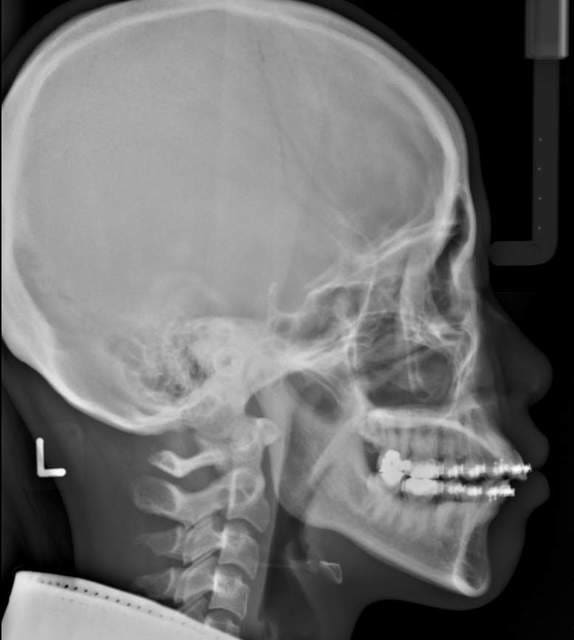

Et voici les radio prise le jour de la réevaluation.

Les condyles sont dans une position plus symmetrique.

L'openbite et l'overjet vont très probablement se regler par intrusion des 7, mais l'apparition du problème et due au non diagnostique de la mauvaise position des ATM